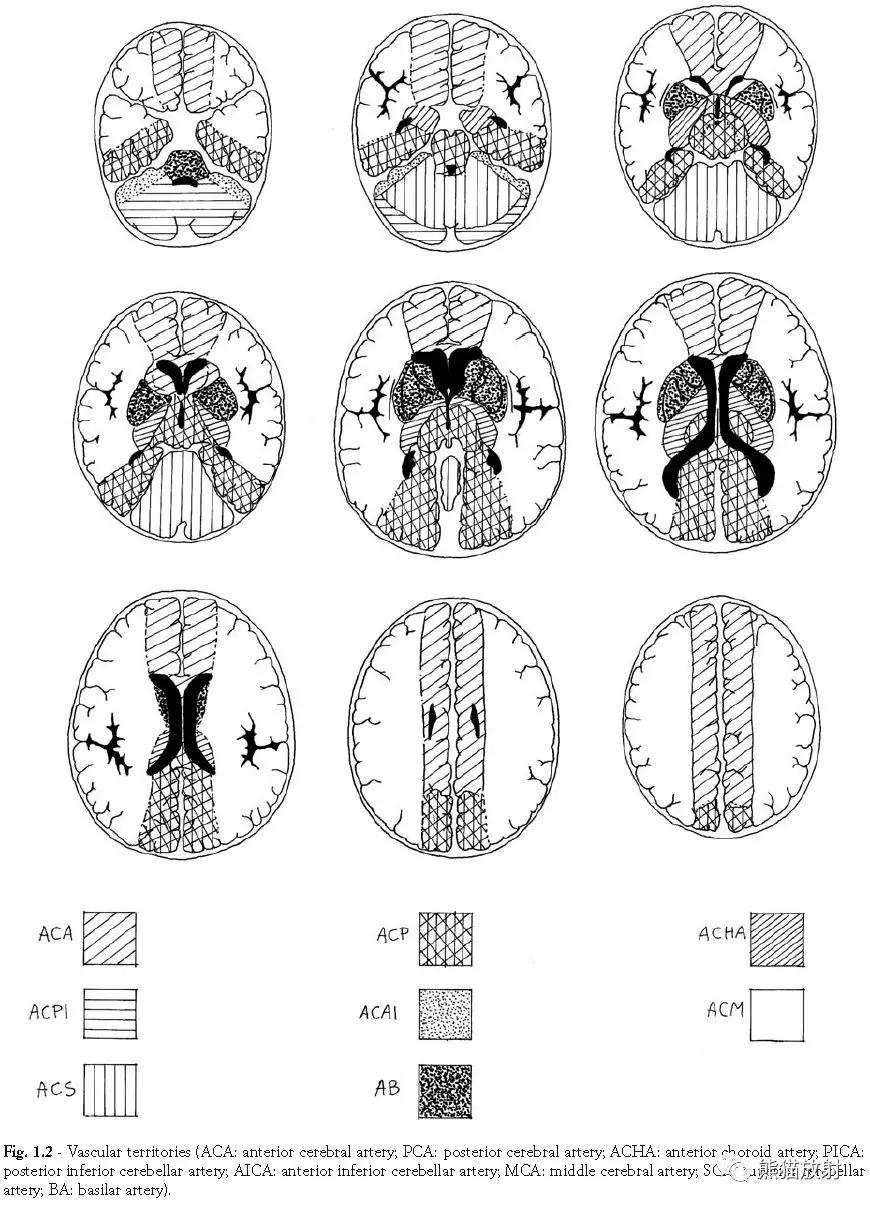

血供区域(ACA:大脑前动脉;PCA:大脑后动脉;ACHA:脉络膜前动脉;PICA:小脑后下动脉; AICA:小脑前下动脉;MCA:大脑中动脉;SCA:小脑上动脉; BA:基底动脉)。